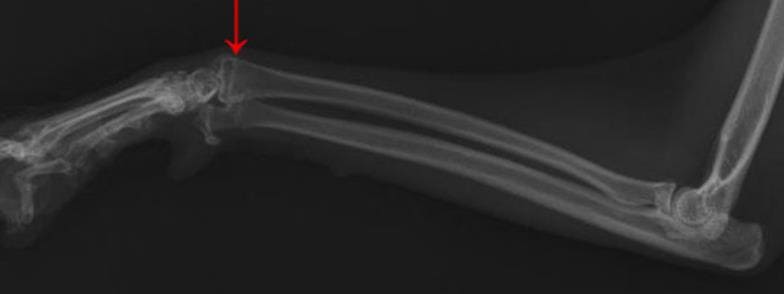

나이가 어린 학생들은 뼈가 생성되면서 관절 사이에 얇은 원판이 만들어지게 되는데 그것이 성장판이라 합니다. 이것이 열렸는지 닫혔는지에 따라 키가 결정되는 만큼 그 시기를 상시적으로 체크하는 것이 중요합니다. 가장 좋은 것은 병원에 방문하여 확인하는 것이지만 비용 혹은 시간적인 여유 때문에 어렵습니다. 그래서 지금 소개해드리는 자가진단을 자주 시행하는 것을 추천드립니다.

성장판 검사 방법 및 시기

위에서 말한 것처럼 성장판은 주로 5세부터 18세까지 활짝 열려있고 그 이후에는 조금씩 닫혀가는데요. 이는 사람마다 굉장히 상이하기 때문에 참고로만 알아두시면 될 것 같습니다. 대부분이 저 시기인만큼 이때 집중적으로 투자하고 관리하는 것이 중요합니다. 키는 한번 정해지면 평생 가기 때문에 영양제, 보조제, 운동 등을 알아보시고 직접 행동으로 하시길 추천드립니다.